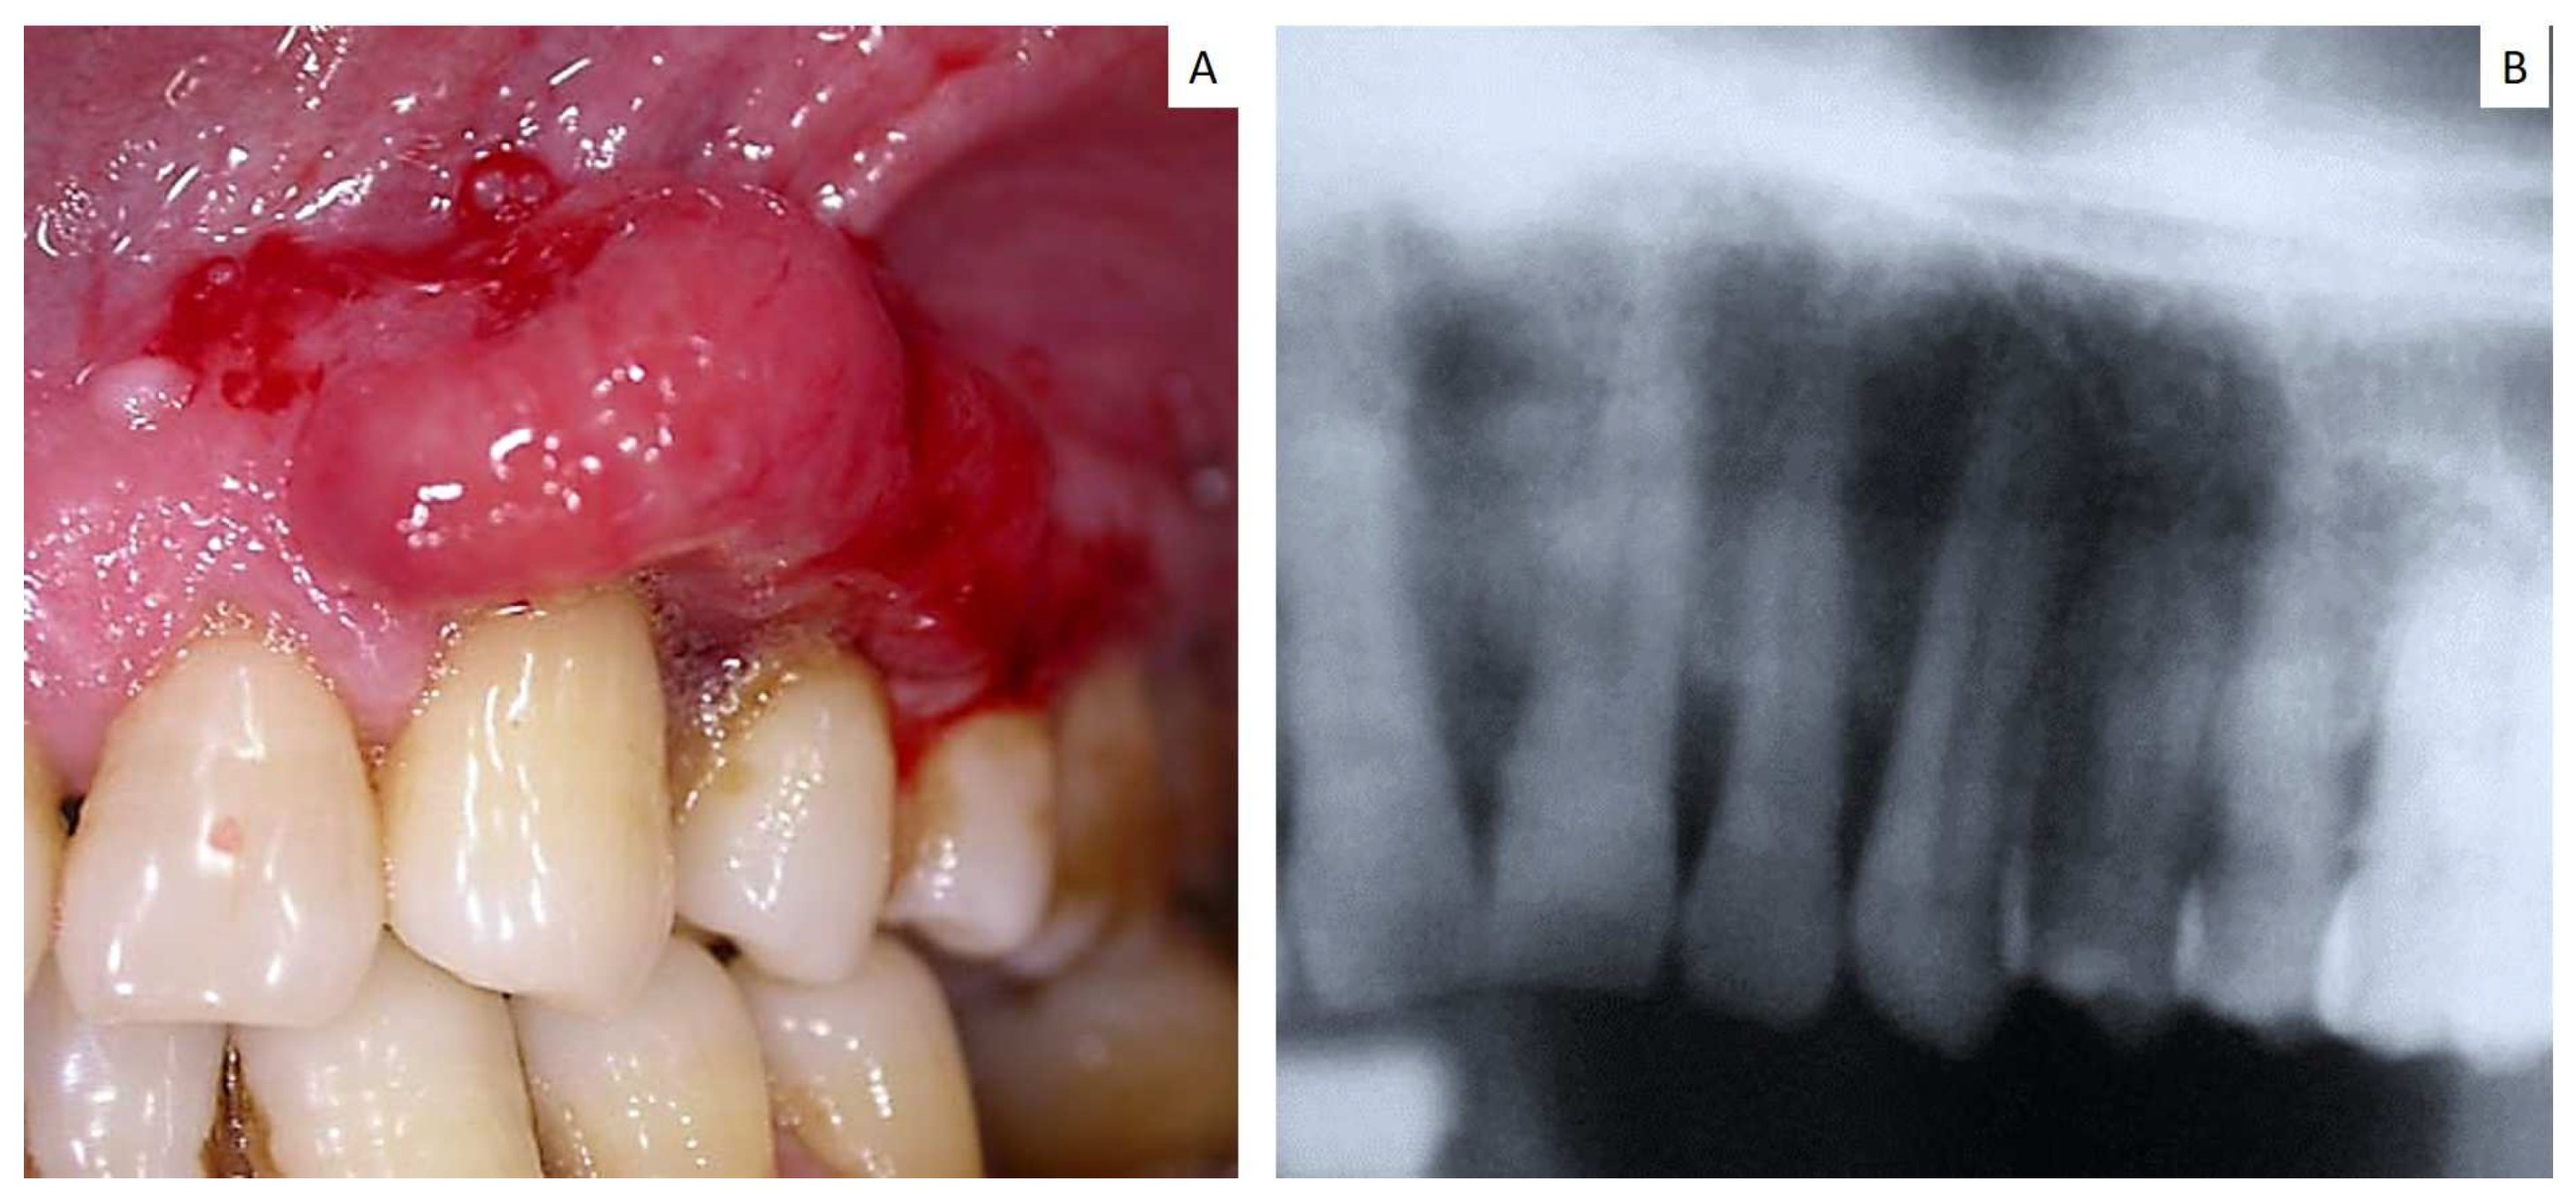

| 17 | 70 | F | Maxillary gingiva Around dental implant | Small cell carcinoma | n.a. | Yes |

| 18 | 62 | M | Maxilla gingiva Around dental implant | Adenocarcinoma | n.a. | Yes |